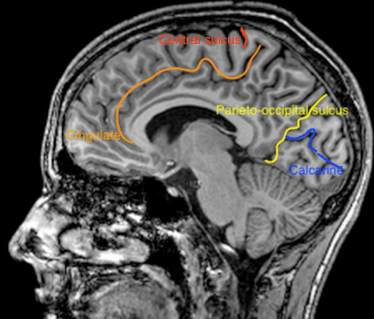

The outer part of the cerebral hemispheres is formed by neocortex, with many gyri and sulci maximizing the brain surface. The sulci that appear first in development, the primary sulci, have a constant pattern, whereas the secundary and tertiary sulci show more interindividual variation.

Figure 1. Primary sulci on parasagittal T1 weighted MRI